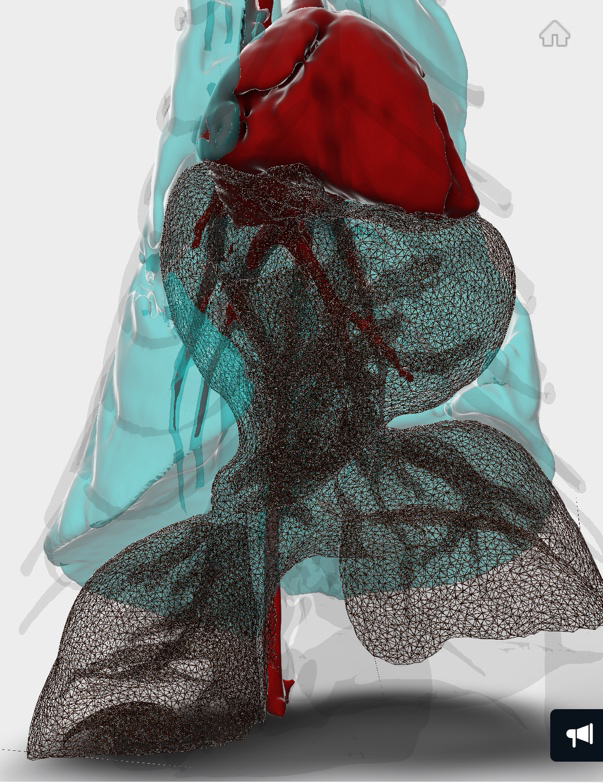

CT検査にて手術前評価

CT検査のデータを3D画像化し肝臓等の逸脱具合を確認